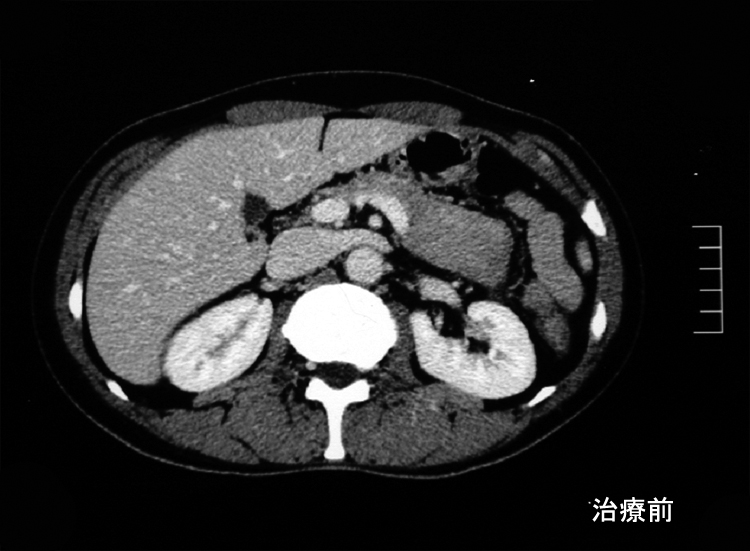

本性例のERCP画像では主膵管とその分枝にあきらかな狭窄所見や壁の不整を認めない。 膵には頭部(CT画像なし),尾部に腫瘤が形成されている。

悪性リンパ腫や膵癌など悪性腫瘍は否定され自己免疫性膵炎と診断し, steroid治療を開始する。約2ヶ月の投与で, 膵、腹腔腫瘤は著明に縮小または消失しました。steroid減量中に黄疸が出現, 画像診断で硬化性胆管炎の合併をうたがいsteroidを増量、黄疸は消失。以後steroid をゆるやかに漸減し中止したが症状の再発はない。